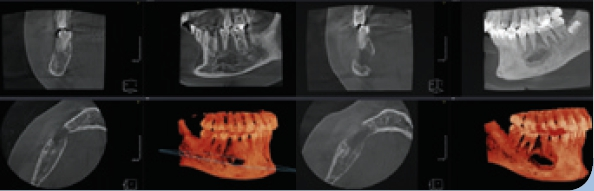

- Die digitale Volumentomographie (DVT) liefert die höchste Auflösung von knöchernen Strukturen, die Darstellung und/oder Differenzierung von Weichgewebe ist jedoch nicht möglich. Vorteile sind die geringen Kosten und die im Vergleich zur CT reduzierten Metallartefakte. Nachteilig hingegen sind der geringe Weichteilkontrast und die Gewebedifferenzierung (Abb. 2 u. 3).

Durch weitere Rechenprozesse können die Daten auf verschiedenste Weise dargestellt werden. Die multiplanaren Rekonstruktionen (MPR) stellen die sinnigste Weiterverarbeitung der Daten dar. Hierbei wird das Volumen durch senkrecht zueinander stehende Ebenen zerlegt, wodurch die Ansichten axial, sagittal und koronal erzeugt werden, ergänzt durch die oberflächengerenderte Ansicht (Abb. 9). Das Angebot entsprechender Bildbearbeitungsprogramme ist vielfältig, zumeist wird das DVT-Gerät mit einer adäquaten Software installiert und eingerichtet – ab diesem Zeitpunkt ist nun der/die Anwender/-in gefordert. In Deutschland ist die Absolvierung eines DVT-Kurses vor Inbetriebnahme eines DVT-Gerätes gesetzlich vorgeschrieben.